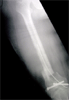

Open comminuted fracture femur treeated with debridement and external fixator

Pre

Op